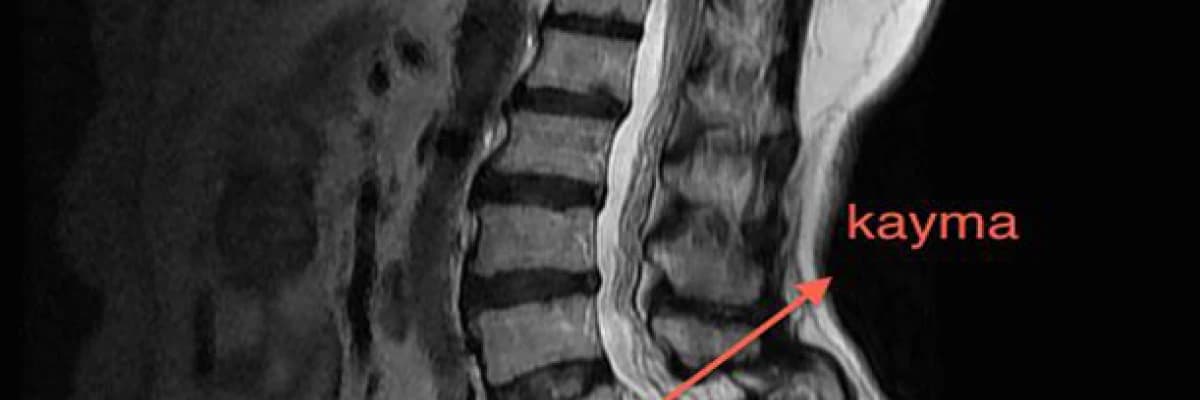

Eğer bu omurgalar üzerinde kayma olursa bu omurgalar üzerindeki düz çizgi bozulur. Bunun sonucunda bir omurga diğerine doğru daha öne çıkar. Bel kayması denilen olay temelde bundan ibarettir.

Bu kayma olayı sonucunda bu omurganın arkasından geçen omuriliğimiz sıkışır ve her iki bacakta ağrı, uyuşukluk yanma gibi hisler meydana gelir. Yürürken sık sık durmak zorunda kalırız.